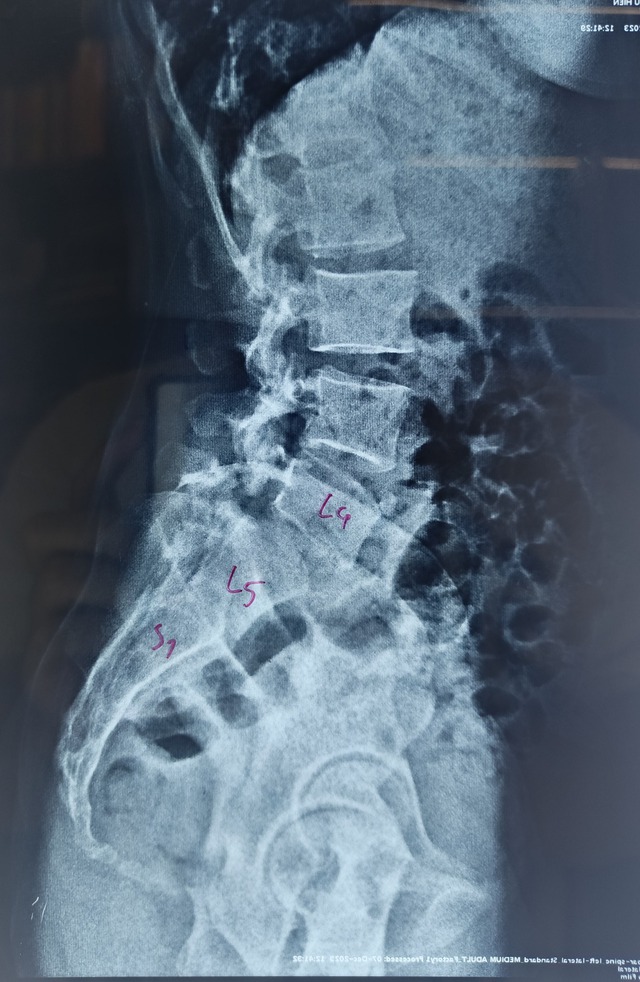

Để minh chứng cho điều này, BS Cao Thanh Phong chia sẻ một trường hợp bị hở eo L4, trượt đa tầng L5/S1 lại được HLV yoga hướng dẫn các bài tập yoga giãn tối đa cơ thể sang 2 bên kèm cúi gập về phía trước, ưỡn tối đa về phía sau. Hình ảnh cho thấy tình trạng bệnh thêm đáng quan ngại, như lời cảnh báo mọi người khi có vấn đề bệnh lý nên đi thăm khám bác sĩ trước, tránh những hậu quả đáng tiếc.

Cột sống bệnh nhân bị hở eo L4, trượt đa tầng L5/S1